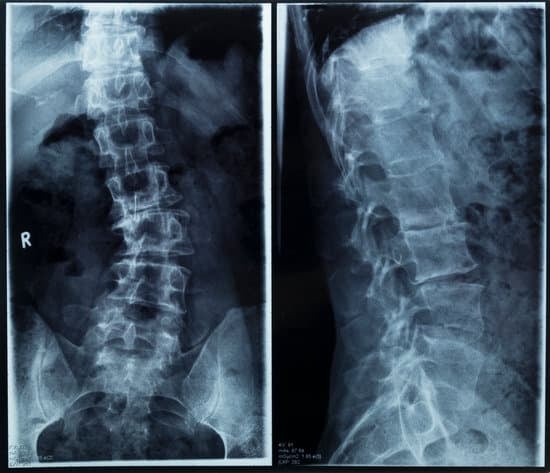

영상 진단

1. X-레이 검사

척추 측만증 진단에서 가장 흔히 사용되는 방법입니다.

X-레이는 척추의 휘어짐 정도와 각도를 측정하는 데 도움을 줍니다.

이를 통해 측만증의 유형과 심각성을 평가할 수 있습니다.